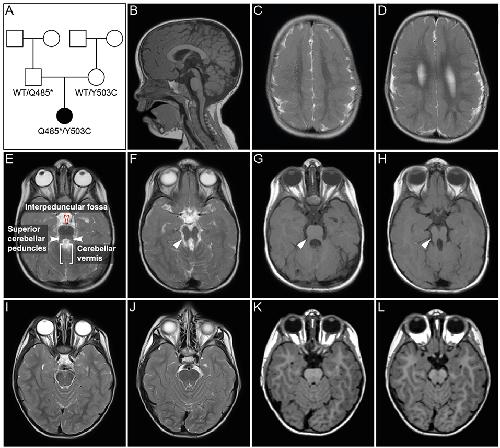

The Frog Xenopus as a Model to Study Joubert Syndrome: The Case of a Human Patient With Compound Heterozygous Variants in PIBF1.,

Ott T,Kaufmann L,Hinderhofer K,Bartram CR,Theiß S,Paramasivam N,Schulz A,Moog U,Evers CM,Granzow M,Seitz A,Blum M,

Front Physiol. January 1, 2019; 10:1664-042X.